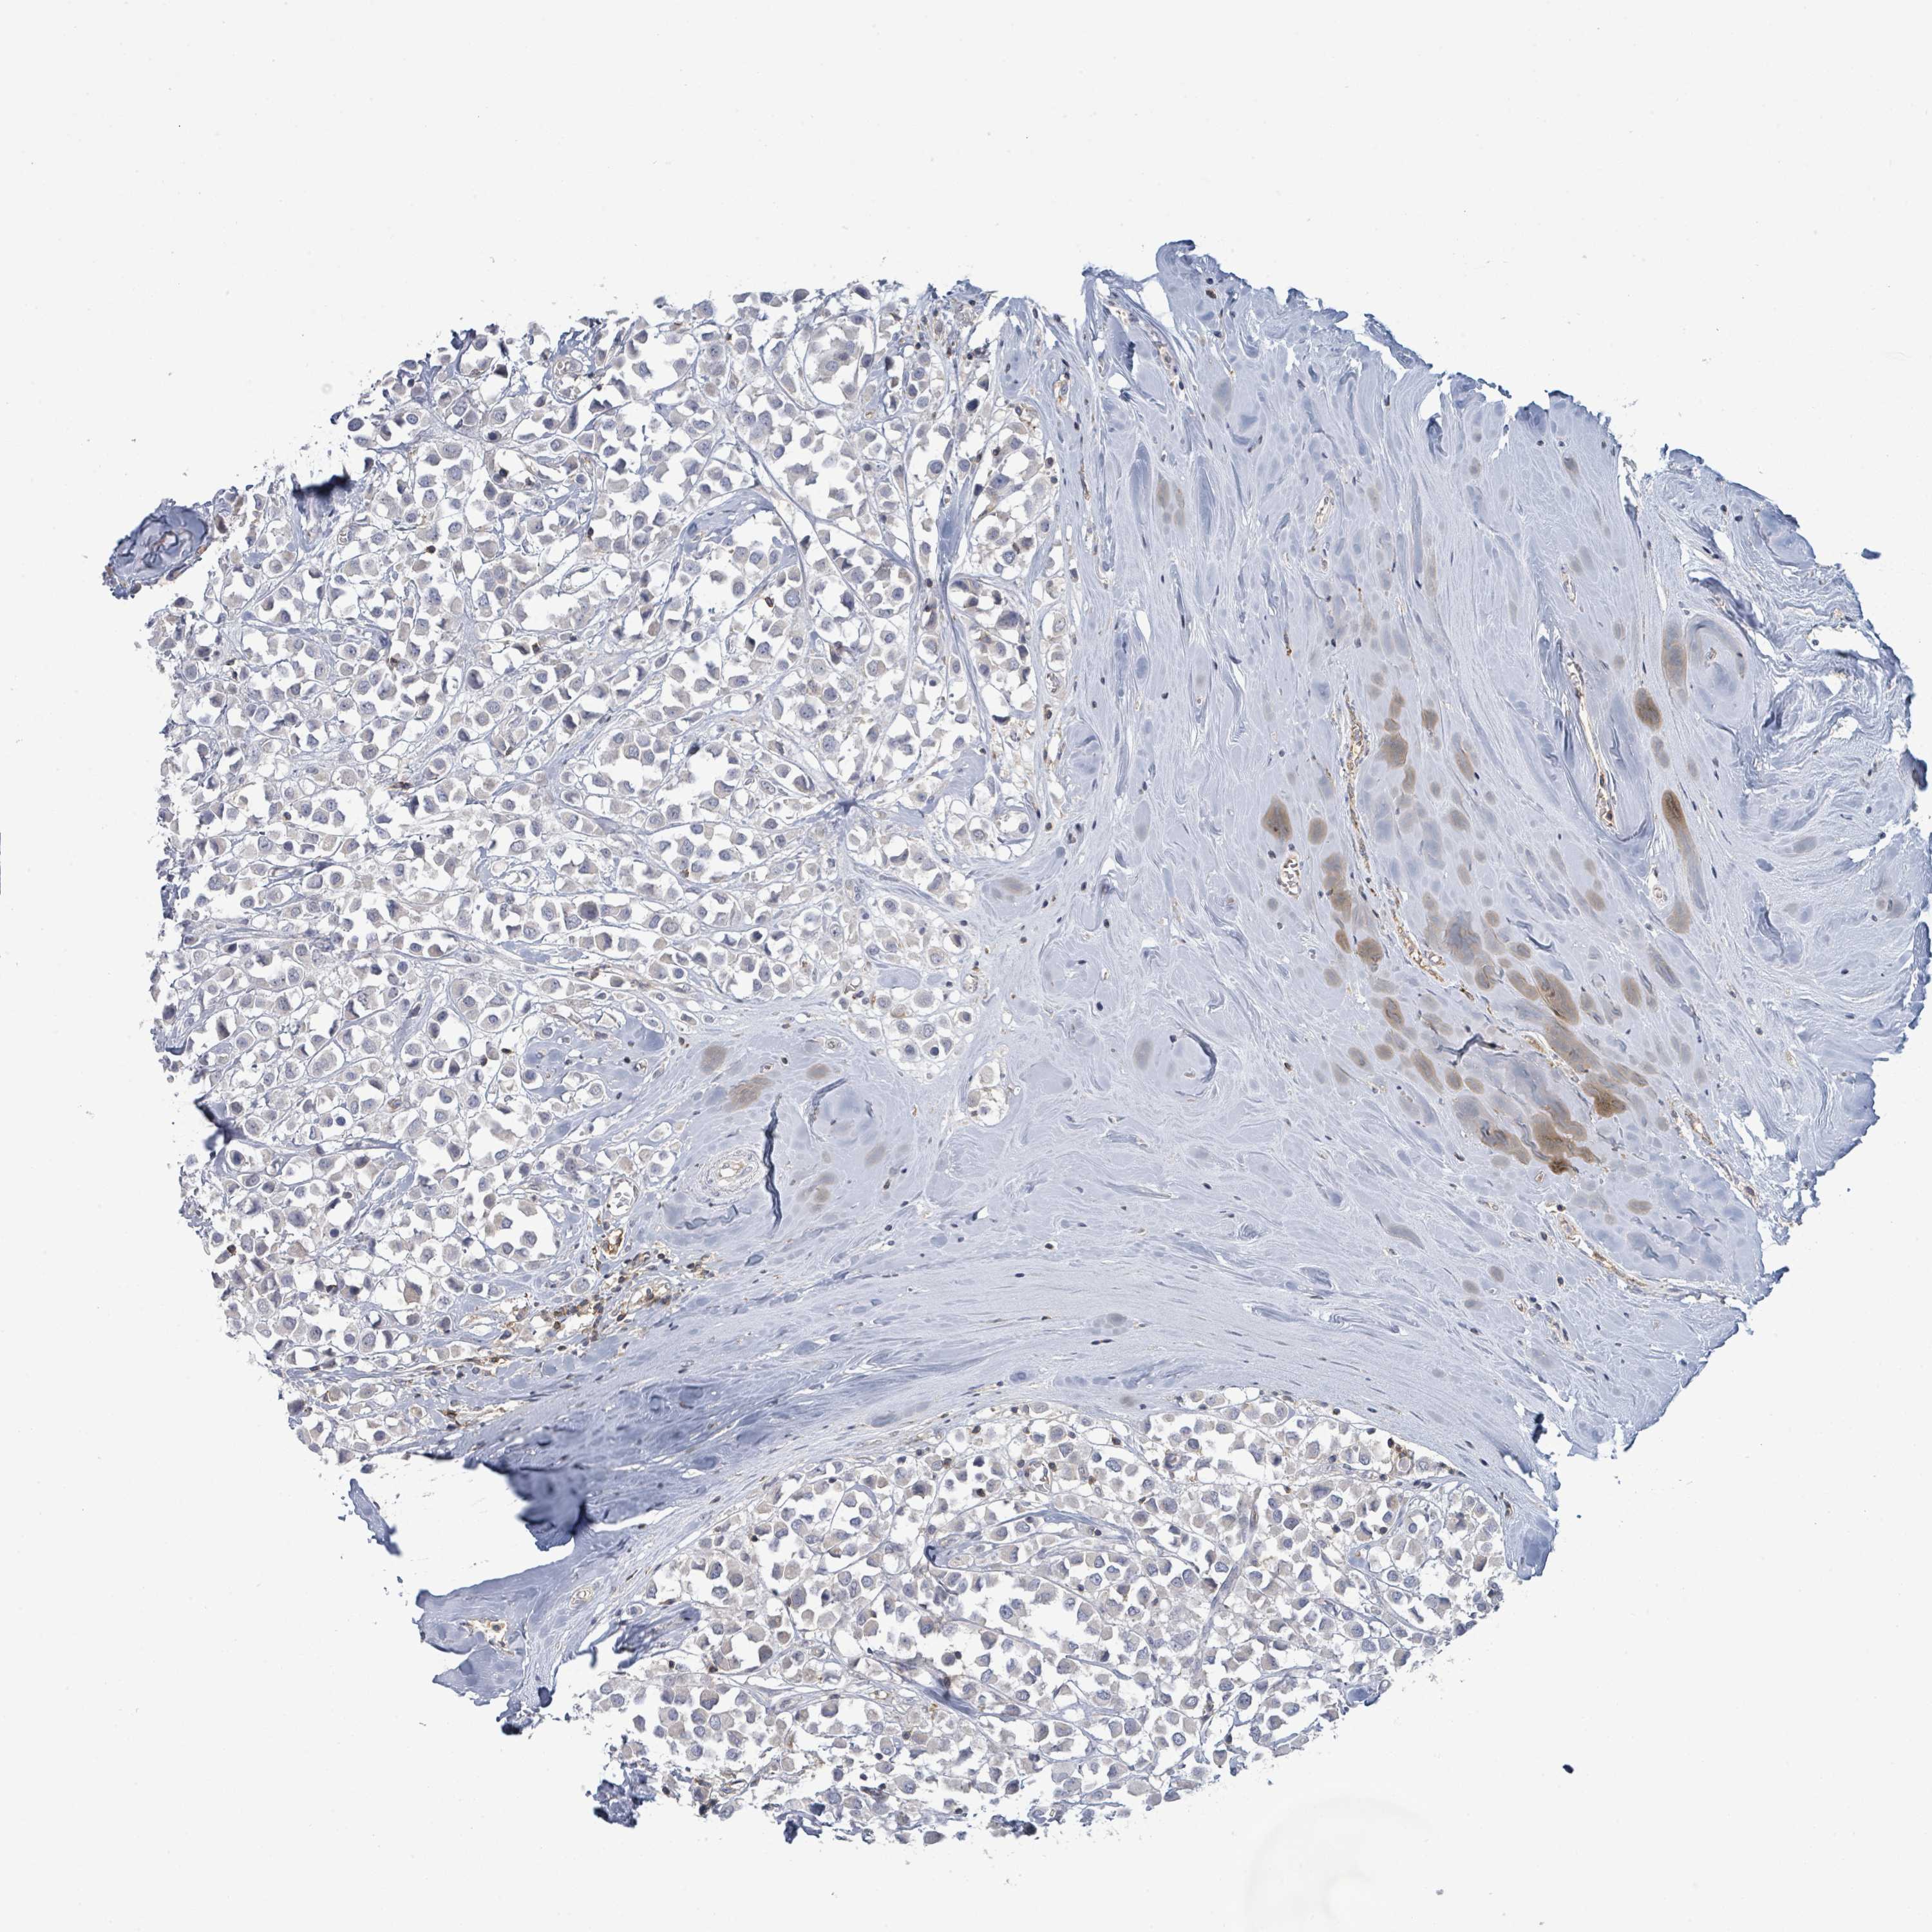

BRCA TCGA BRCA VALIDATION PROTEIN EXPRESSION

ANTIBODIES

AND

VALIDATION